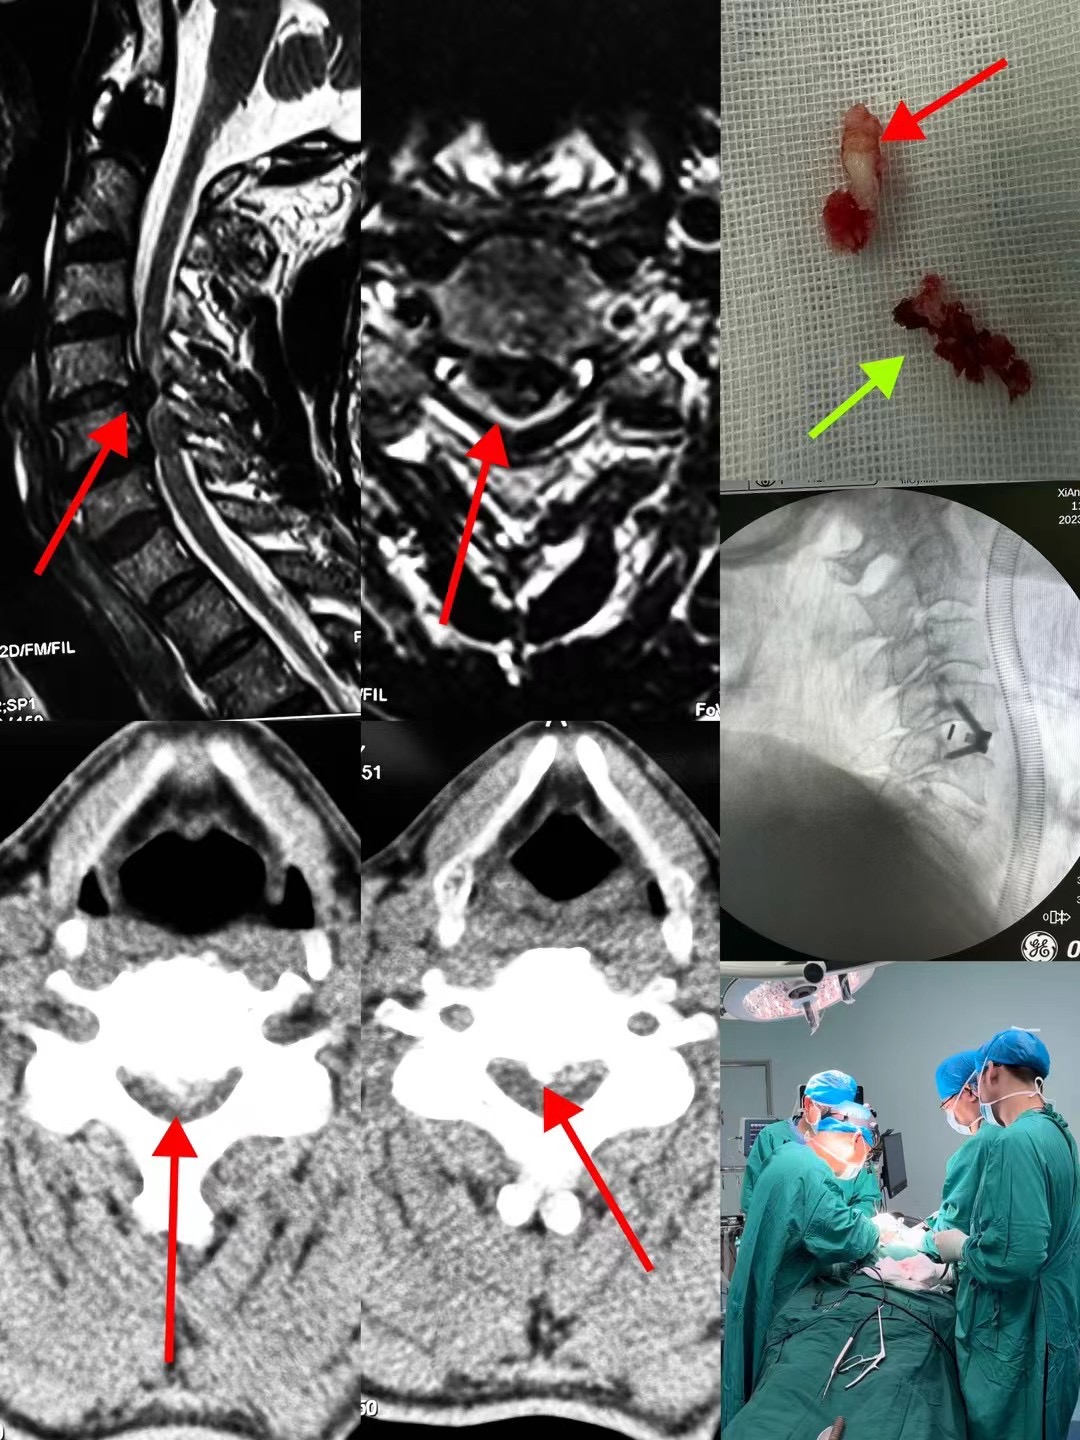

近日,骨二科臧全金副主任医师团队成功完成一例复杂脊柱手术。患者为颅底凹陷症合并脊柱侧凸,已经在西安多家医院门诊就诊,并在某知名三家医院住院治疗,但均未获得良好诊治。后来在北医三院主任医师推荐下来到臧全金副主任医师处治疗。接诊后,臧全金发现患者为严重的颅底凹陷症合并脊柱侧弯,实属罕见,治疗难度大,风险高。但正是这样的病例激起了他的兴趣,术前其带领的治疗团队详细研读了患者的影像资料,制定了详尽的手术方案,于近日一期完成了颅底凹陷症的解剖复位和脊柱侧凸截骨矫形术,术后患者恢复良好,无任何神经并发症。颅底凹陷症合并寰枢椎脱位、脊柱侧凸两种疾病任何任何一种在脊柱外科都属于高难度复杂手术,在脊柱外科领域都属于珠穆朗玛峰般的存在,西北地区只有少数几家三甲医院开展此类疾病的手术治疗,而能够主刀完成这种手术的医生少之又少。看到孩子顺利完成手术,患者家属感到特别高兴,再三感谢臧全金副主任医师团队高超的手术技艺以及过人的胆识,为自己的孩子解决了困扰多年的疾病。

像这样的高难度颈椎手术,臧全金副主任医师带领曹凯博士、郭帅博士的团队近期已完成了多例,均取得了良好的手术效果。一例外省的颈椎肿瘤患者,慕名从省外来到骨二科,在臧全金副主任医师团队的精心治疗下,一期前后路切除肿瘤,完成颈椎重建,术后神经功能得到恢复。多例颈椎后纵韧带骨化患者,椎管内占位达到椎管前后径的70-80%,脊髓被压得只剩下一条线,臧全金带领的团队精雕细琢,为患者完成减压,术后患者从蹒跚行走到灵活小跑;颈椎间盘突出压迫脊髓瘫痪患者在臧全金团队的治疗下从卧床到下地行走…………为了解决患者的病痛,臧全金急患者之所急,近一周从家中赶往医院为两次颈椎脱位脊髓损伤患者行急诊手术,第一时间挽救患者脊髓功能。很多病例不一例数。

把颈椎病和上颈椎疾病作为研究的方向,臧全金副主任医师团队在过去的几年里取得了良好的成绩。臧全金所设计的上颈椎内植物获得了授权国家发明专利三项,并且内植物的临床应用获得了两项国内国际第一;所研究的内容发表在脊柱外科专业领域知名期刊《Spine》等杂志上;因为在颈椎人工关节方面的研究,被选为中国康复医学会颈椎学会人工椎间盘学组委员;上颈椎疾患的治疗效果获得了顶级专家的认可和推荐,同时作为副主编书写的《上颈椎疾病诊治与病例精析》将于近期在人民卫生出版社出版。